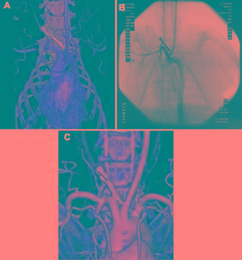

| Abstract | OBJECT: Sphenopalatine ganglion stimulation activates perivascular vasodilatory nerves in the ipsilateral anterior circle of Willis. This experiment tested whether stimulation of the ganglion could reverse vasospasm and improve cerebral perfusion after subarachnoid hemorrhage (SAH) in monkeys. METHODS: Thirteen cynomolgus monkeys underwent baseline angiography followed by creation of SAH by placement of autologous blood against the right intradural internal carotid artery, the middle cerebral artery (MCA), and the anterior cerebral artery. Seven days later, angiography was repeated, and the right sphenopalatine ganglion was exposed microsurgically. Angiography was repeated 15 minutes after exposure of the ganglion. The ganglion was stimulated electrically 3 times, and angiography was repeated during and 15 and 30 minutes after stimulation. Cerebral blood flow (CBF) was monitored using laser Doppler flowmetry, and intracranial pressure (ICP) was measured throughout. The protocol was repeated again. Evans blue was injected and the animals were killed. The brains were removed for analysis of water and Evans blue content and histology. RESULTS: Subarachnoid hemorrhage was associated with significant vasospasm of the ipsilateral major cerebral arteries (23% ± 10% to 39% ± 4%; p < 0.05, paired t-tests). Exposure of the ganglion and sham stimulation had no significant effects on arterial diameters, ICP, or CBF (4 monkeys, ANOVA and paired t-tests). Sphenopalatine ganglion stimulation dilated the ipsilateral extracranial and intracranial internal carotid artery, MCA, and anterior cerebral artery compared with the contralateral arteries (9 monkeys, 7% ± 9% to 15% ± 19%; p < 0.05, ANOVA). There was a significant increase in ipsilateral CBF. Stimulation had no effect on ICP or brain histology. Brain water content did not increase but Evans blue content was significantly elevated in the MCA territory of the stimulated hemisphere. CONCLUSIONS: Sphenopalatine ganglion stimulation decreased vasospasm and increased CBF after SAH in monkeys. This was associated with opening of the blood-brain barrier. |